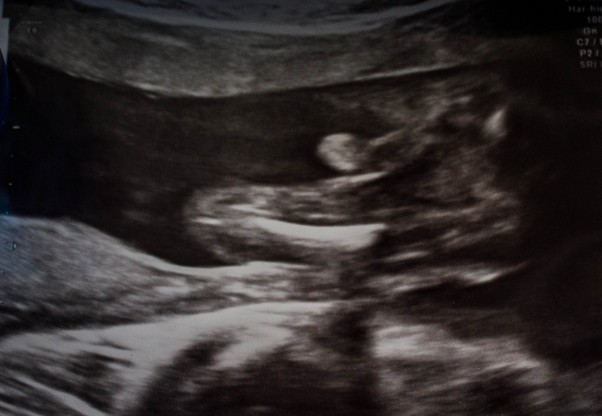

32 tc....

no i juz 3 usg 3 d za nami....młody zasłonił sie rączkami ...i nici z super foty profilowej, ale wazymy już aż 2020 kg...i mamy sporo sadełka co bardzo mnie cieszy bo czuje się bezpieczniej wiedząc ze masa sie zwięksa mimo ze ja chudne nadal...;)......no i najważniejsze....jeszcze miałam odrobinę nadzieji ze może bedzie dziewucha słodka z kucykami miłą która nie walczy od rana z bratem a tu niestety ....jajeczka latały po ekranie i nie dawały się niezauwazyc...;)czyli bedzie na 99% Julian MArcel....;)bede mamą cóy i 3 chopów...:)